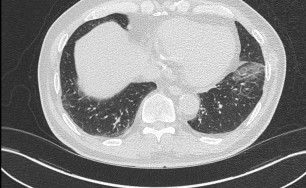

폐기종

폐기종 증상과 합병증

숨쉬기가 힘들다, 숨이 찬다, 가슴이 답답하다, 기침을 한다 이런 증상들은 폐기종을 의심해 볼 수 있기 때문에 가급적 제대로 된 진찰을 받아보시길 권해드립니다.

숨케어한의원에서는 전화예약을 받고 있습니다. 내원시 엑스레이, CT사진, 폐기능검사지를 가지고 오시면 자세한 상담이 가능합니다.